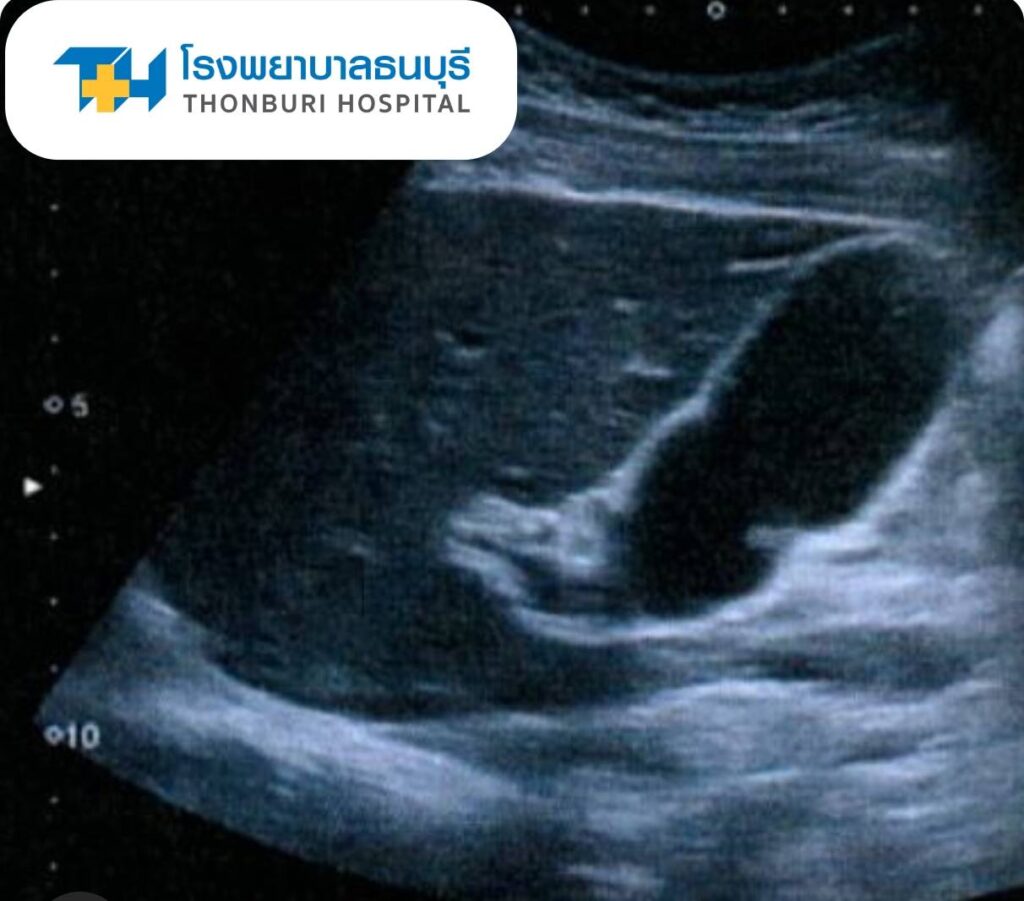

การวินิจฉัยโรคนิ่วในถุงน้ำดีแพทย์จะเริ่มจากการซักประวัติ ตรวจร่างกาย และใช้การตรวจทางภาพถ่ายเพื่อยืนยันการวินิจฉัย ได้แก่

อัลตราซาวนด์ช่องท้อง (Ultrasound): เป็นวิธีที่นิยมที่สุด